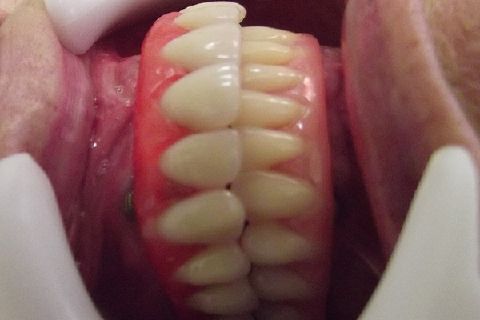

Protocolo Duplo Sendo Superior All-On-4

Caso clínico, 03 de Abr de 2014

Fotos do caso